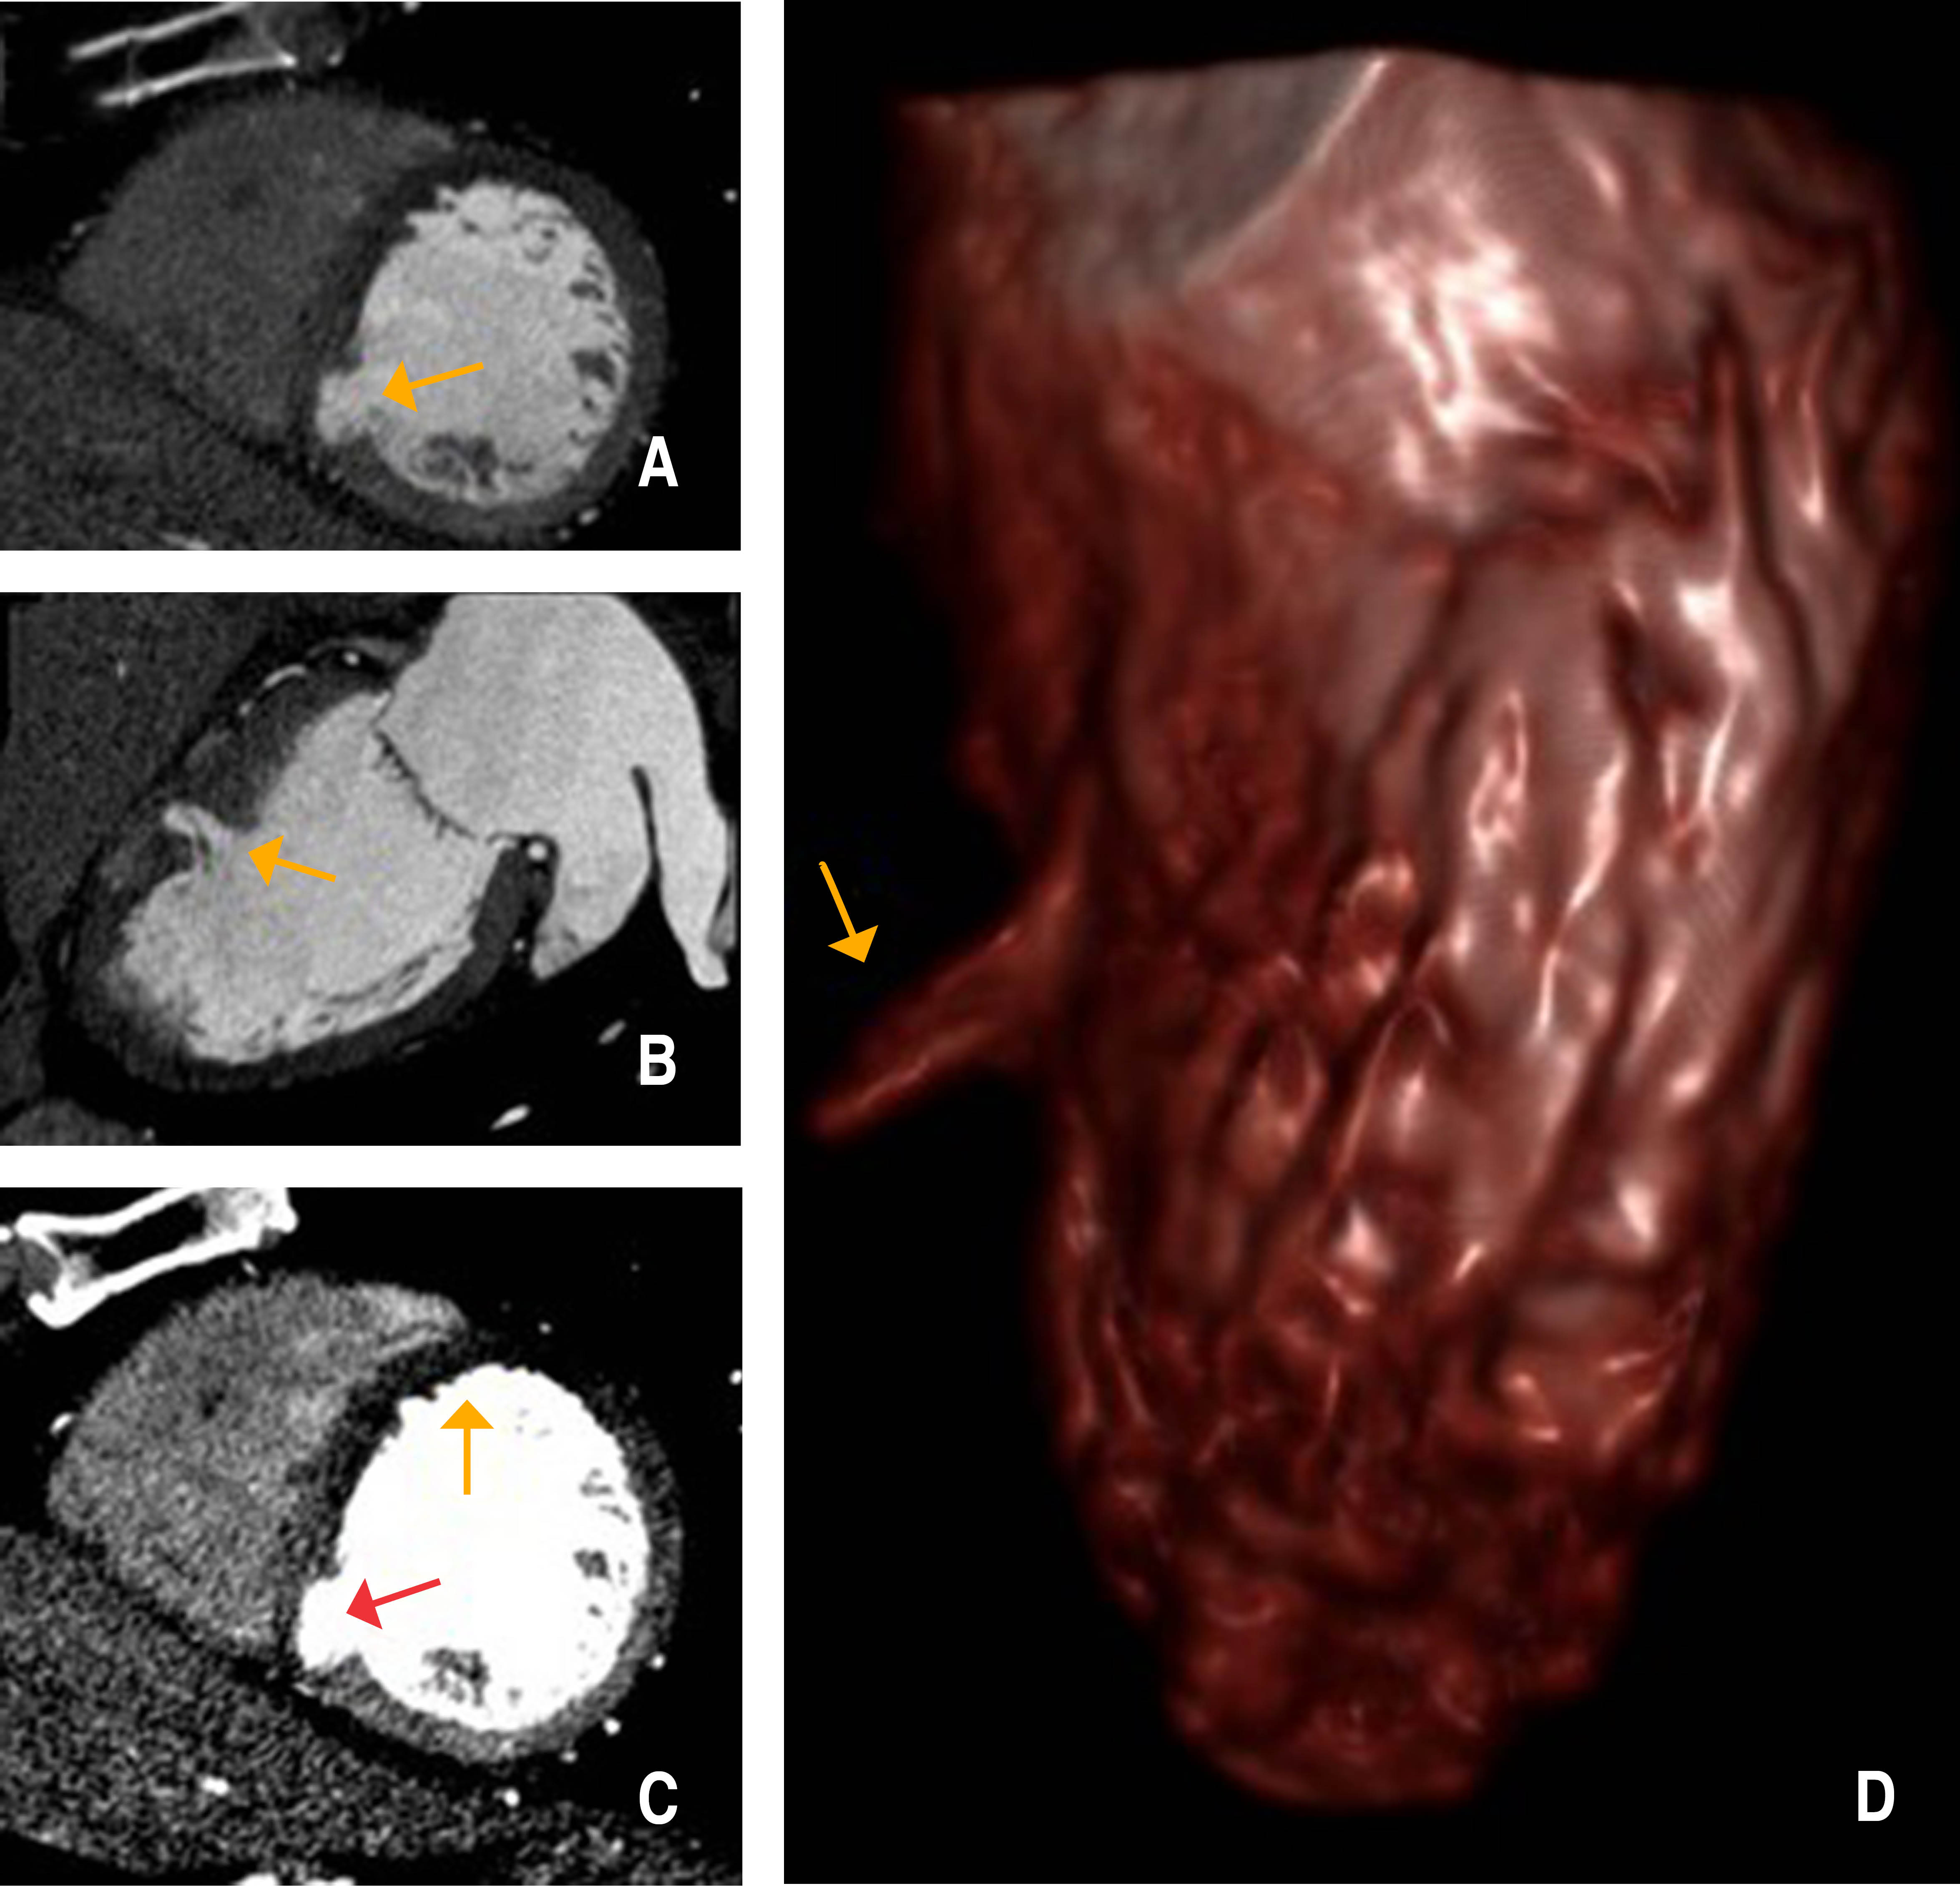

Divertículo ventricular congénito izquierdo aislado en adulto: un hallazgo inusual en infarto de miocardio asociado a cocaína

El divertículo ventricular congénito izquierdo (DVCI) consiste en una bolsa de salida de endocardio, miocardio y pericardio, que a menudo se presenta como una proyección de la pared libre del ventrículo, con un cuello estrecho que conecta la cavidad con el ventrículo propiamente dicho. Aunque a menudo se asocia con otras anomalías congénitas cardiacas y extracardiacas, también puede presentarse solo, como un hallazgo incidental en pacientes adultos. Debido a su baja prevalencia general y variabilidad en la presentación, aún no se ha definido un tratamiento estandarizado. Presentamos el caso de un paciente adulto con infarto de miocardio (IM) asociado a cocaína, en el que se evidenció un DVCI septal mediante angio-TC coronaria. Se descartaron otras anomalías cardiacas y el paciente respondió bien al tratamiento médico tras el cateterismo cardiaco; por lo que se prefirió el seguimiento médico y no la cirugía.

Figura 3